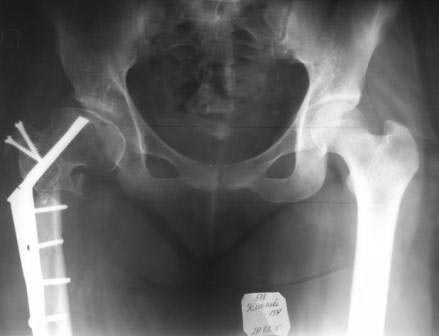

Уважаемые коллеги, обратилась девушка 1991г.р. 2 года назад оперирована в другой области по поводу диспластического коксоартроза ( похоже Мак Маррея, фиксация ЦИТО –Бакичарова), вот уже почти два года ходит с двумя костылями, наступать на ноги не может из-за боли, ногу активно поднять не может, активные движения в т/б суставе резко ограничены из-за боли, пассивные: 5/0/90гр, приведение - 20, отведение - 10гр, ротация-около -30, но болезненная. беспокоят боли в основном в обл ложного сустава, при движениях и пальпации в обл т/б сустава болей нет.

На Р-грамме, похоже, клинок пластини сломан, сращения нет.

Выраженность артроза относительная. Особенно учитывая минимальные субъективные ощущения пациентки в самом суставе, а это главный критерий при оценке необходимости эндопротезирования. Суставная поверхность, судя по рентгенологической картине имеет еще большой запас прочности. Налицо основная проблема - ложный сустав подвертельной области.Я попробовал бы реостеосинтез в положении coxa valga.Металлоконструкция зависит от возможностей вашей клиники. Long Gamma, как пример.

Здесь результат неудачной операции по увеличению нагрузочной площади при дисплазии тазобедренного сустава. Причина осложнения с болевым синдромом и потерей опороспобности - неудачный выбор имплантата, а также отсутствия опыта.

Пластина Бакычарова предназначена для лечения чрезвертельных переломов, где силовой вектор находится косо, и в такой конструкции невозможно создать поперечную компрессию. Поэтому перед выбором фиксатора необходимо тщательно обдумать, какой из фиксаторов подойдет для лечения ложного сустава. Иначе следующее осложнение может быть катастрофическим, потому что в результате осложнения можно потерять проксимальное бедро. А без проксимального бедра меняется механика тазобедренного сустава, которая может усложнить установку ножку протеза!

Предложенный БИОС с рассверливанием канала рекомендуется для лечения ложных суставов в диафизарной зоне! А здесь патология находится в межвертельной зоне и нет нужды устанавливать гвоздь. Любой гвоздь, включая цефаломедуллярные, не позволяет создать компрессию! Вместо БИОС 95 градусный Blade Plate, который минимизирует операцию и создаст компрессию в зоне!

Здесь вариант установки 95 градусной пластины при варусной остеотомии.

Уважаемые коллеги. Больная оперирована 06.03.15г клинок был сломан, и пока его с трудом удалили, от неполноценного вертела почти ничего не осталось, сломанный шуруп тоже удален, шейка совсем короткая, , ШДУ около 95гр, из-за сильного остеопороза при сверление в положении чуть вальгуса наружная стенка крошится , и еще что интересно при первой операции головка бедра оказалось фиксирована в положении ретроверсии примерно 10-15 гр.. и с трудом удалось выпрямить головку и шейку до 0 гр. , укорочение было чуть больше 1см , п/о -2см, пока фиксация - гипсовый сапожок с деротатором. Дальше как быть? Может временно фиксировать кокситной повязкой( канда каст)?